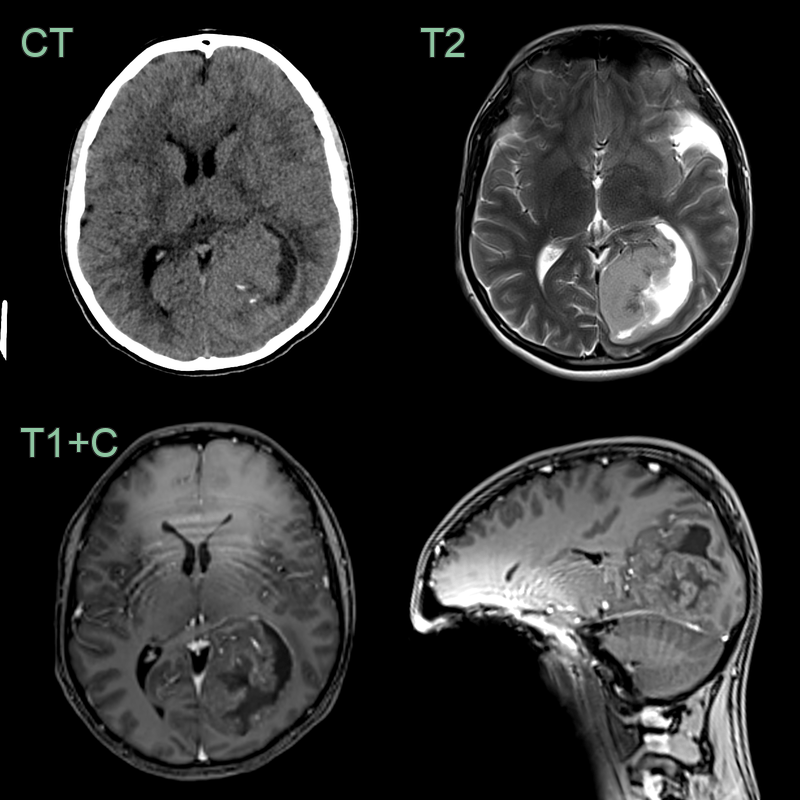

- CT:

- Hyperdense to isodense mass

- Calcifications in 50% of cases

- Variable enhancement

- MRI:

- T1: iso- to hypointense

- T2: hyperintense with potential cystic components

- FLAIR: hyperintense

- DWI: variable restriction

- T1 C+ (Gadolinium): heterogeneous enhancement

- Specific features:

- Intracranial: "plastic" moulding to ventricular shape

- Spinal: eccentric location within central canal, "cap sign" of haemosiderin at tumour poles